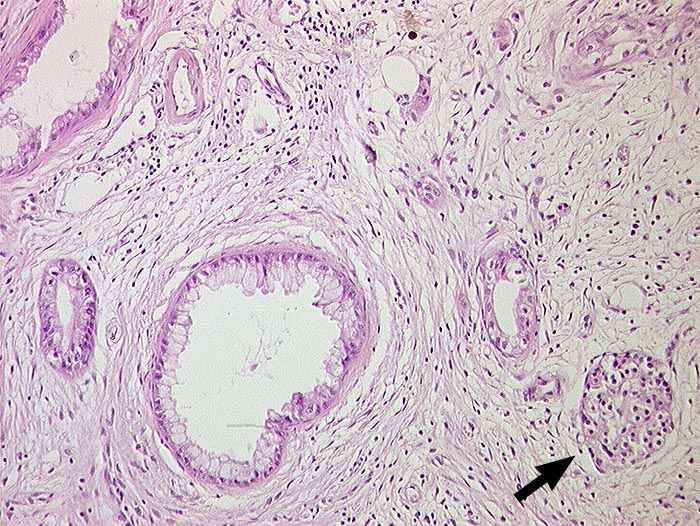

Gut differenziertes duktales Adenokarzinom

Im desmoplastischen Stroma liegen irregulär verstreut Drüsenschläuche mit hochprismatischem Epithel und minimalen Zellatypien. Vom normalen Pankreasparenchym sind lediglich einzelne Inseln übriggeblieben.

Pankreasgangstenose. Nervenscheideninvasion und Lymphangiosis carcinomatosa.

Das Fehlen einer organoiden Anordnung der ansonsten kaum atypischen Drüsen hilft zur Abgrenzung von einer chronischen Pankreatitis.